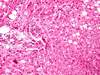

What type of tumour are these images? Describe why.

Normal glandular epithelium with crypts